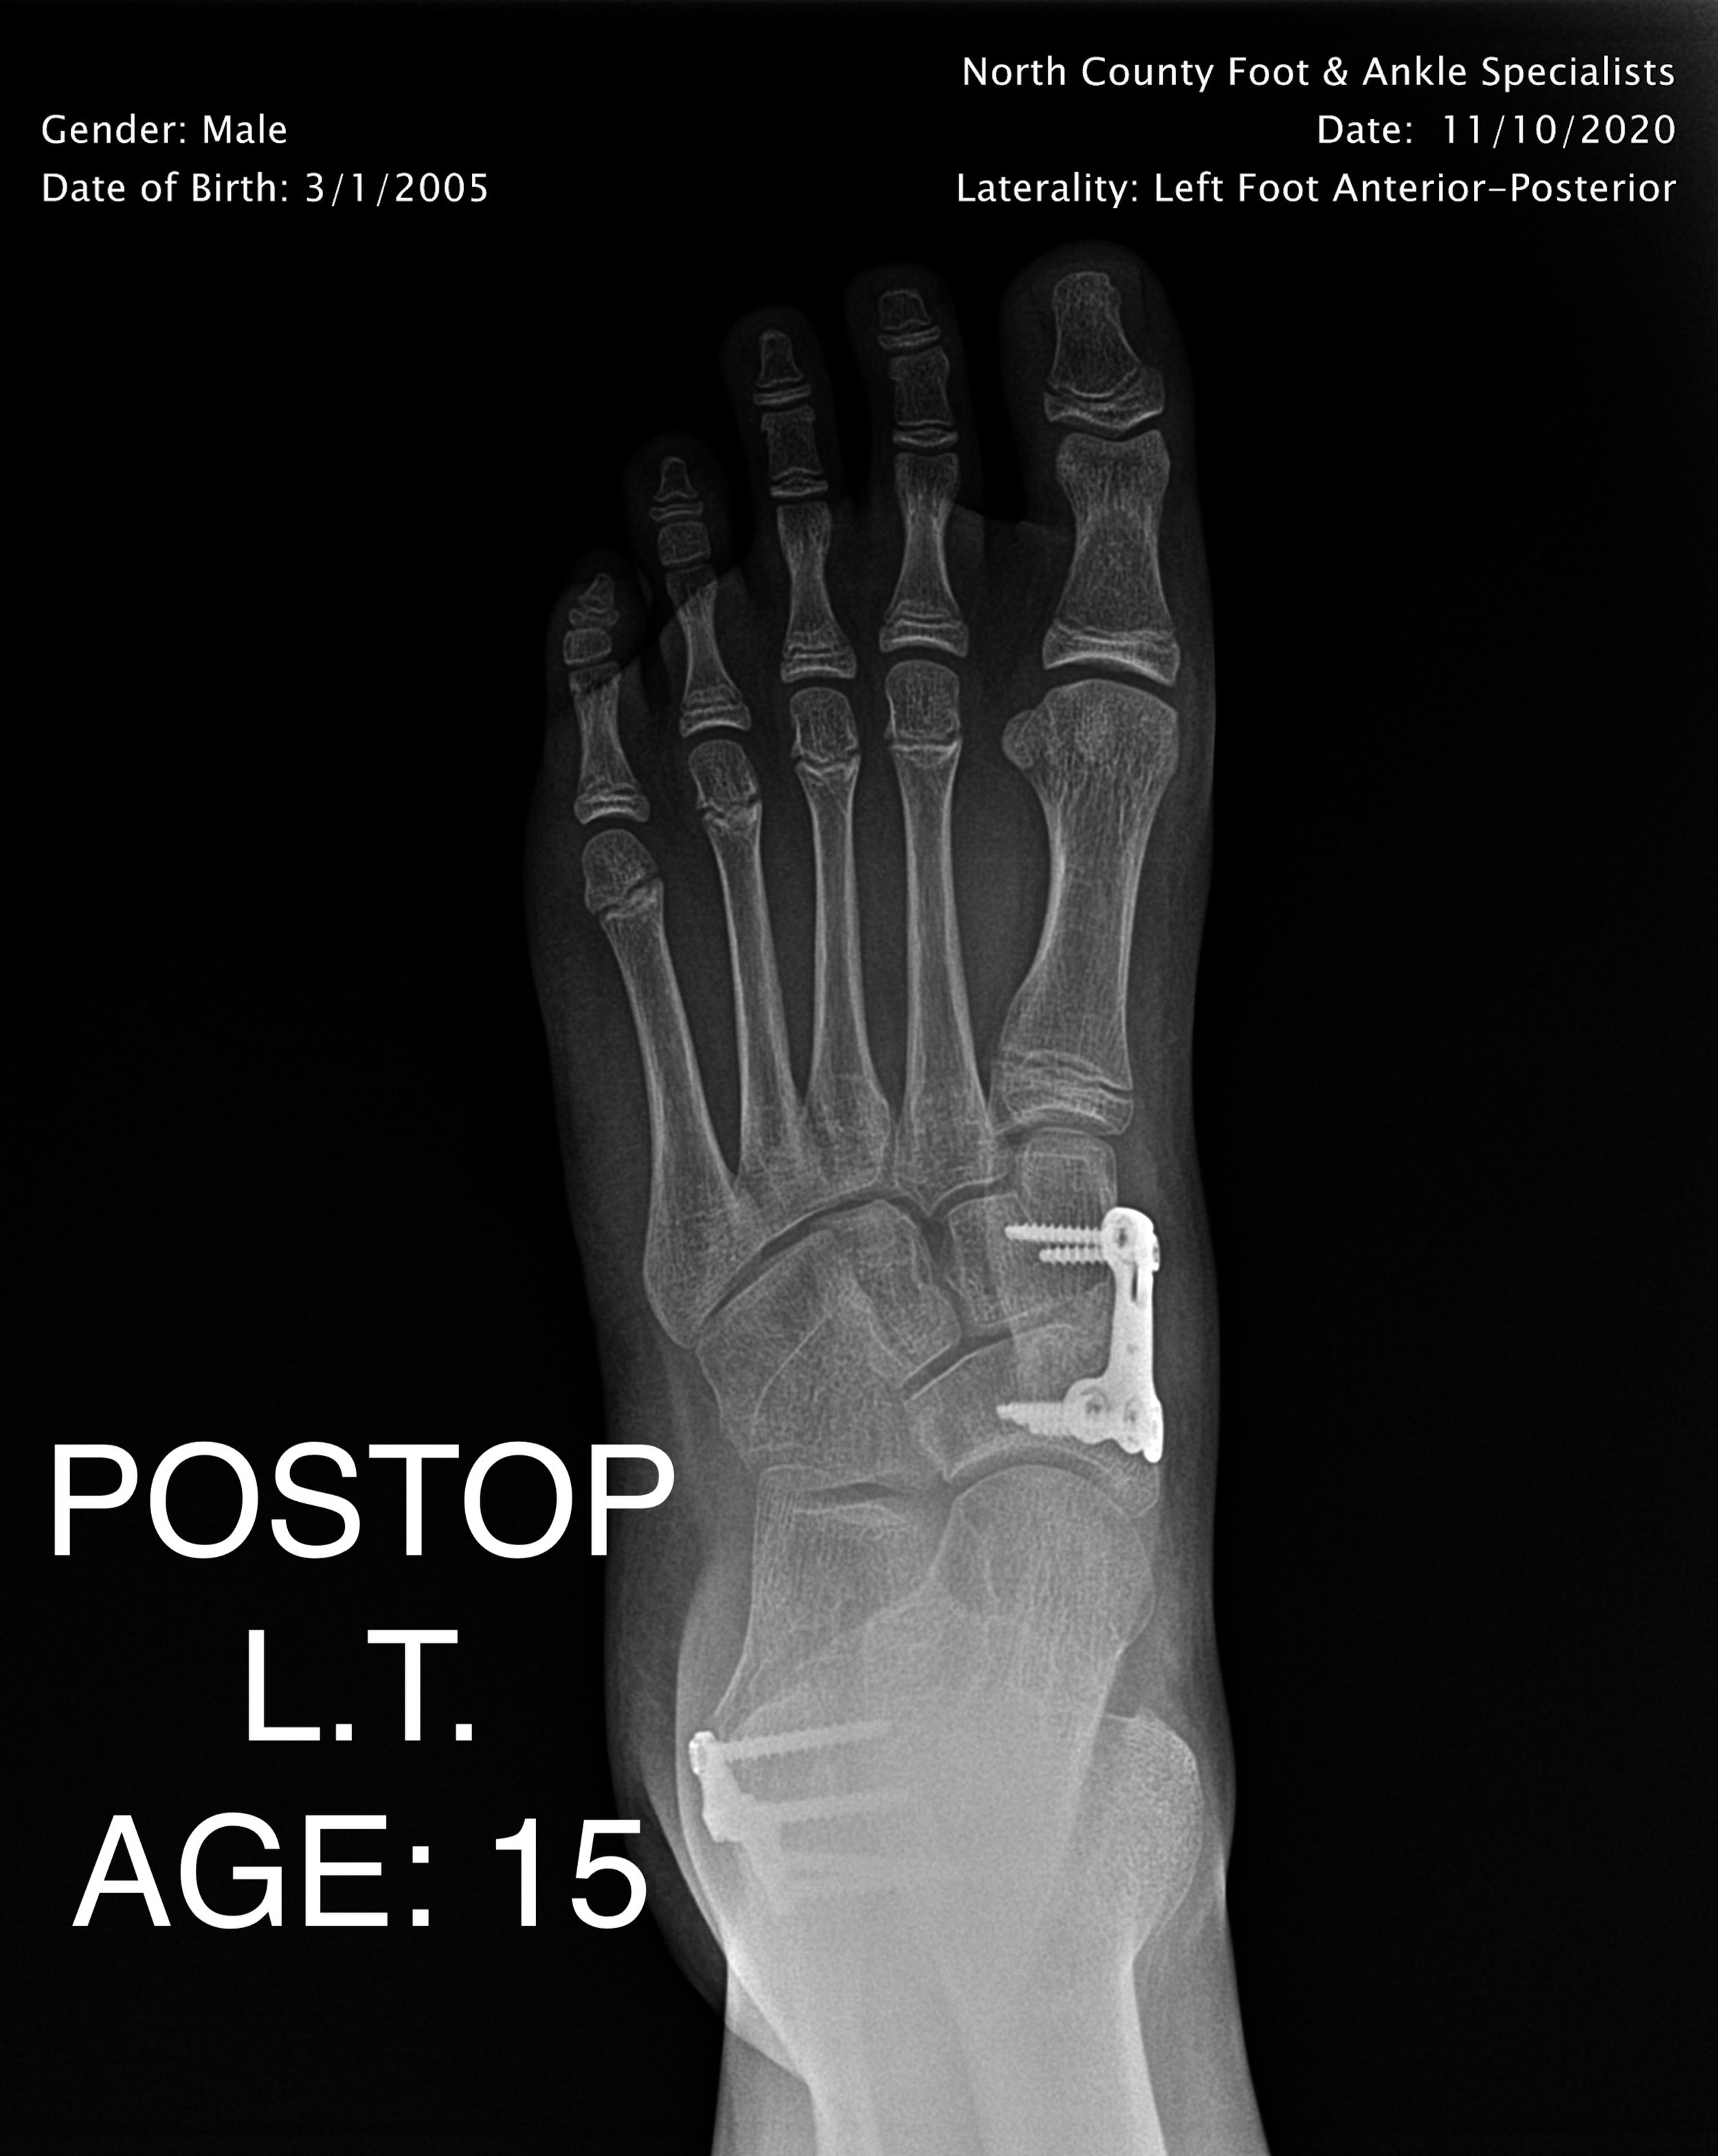

PEDIATRIC FLAT FOOT

LAPIDUS